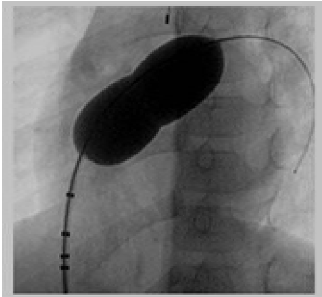

- Đẩy bóng trên guidewire cứng lên lỗ thông liên nhĩ. Bơm bóng bằng thuốc cản quang tại vị trí lỗ TLN. Ngừng bơm khi xuất hiện rõ eo bóng.

- Đo kích thước eo bóng trên phim chụp mạch dựa vào các điểm mốc trên bóng.

- Làm xẹp bóng, rút bóng ra khỏi cơ thể. Đo lại kích thước bóng bằng cách bơm một lượng thuốc cản quang tương tự.

- Xác định kích thước lỗ TLN theo ba phương pháp: trên phim chụp mạch, trên siêu âm qua thực quản, và phương pháp đo trực tiếp ở ngoài.

Hình 1. Đo kích thước lỗ thông bằng bóng